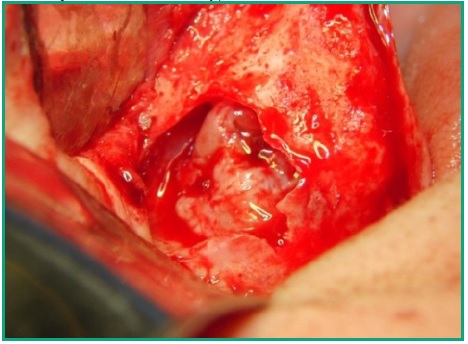

Procedimiento quirúrgico. Mediante la anestesia local correspondiente se procede a realizar una incisión crestal desde la zona tuberosal hasta cerca de la línea media, con una incisión relajante a ese nivel. Previamente a la misma se hizo una punción exploratoria dando como resultado la extracción de un contenido tipo muco purulento. Se elevó un colgajo de espesor total desde adelante hacia atrás, observándose en la zona posterior una fenestración ósea por donde drena abundante contenido mucopurulento (Fig. 6).

Se procede a hacer ostectomía con instrumental rotatorio y abundante irrigación con suero fisiológico, con la finalidad de agrandar la fenestración para facilitar la visibilidad. Con curetas de elevación sinusal se realiza la eliminación total de la lesión mediante la técnica de enucleación y curetaje, procediendo luego a hacer la exéresis del tabique óseo que divide dicha patología (Figs. 7, 8, 9). Por último se realizó un cierre mediante sutura continua con nylon 5 cero (Fig. 10).